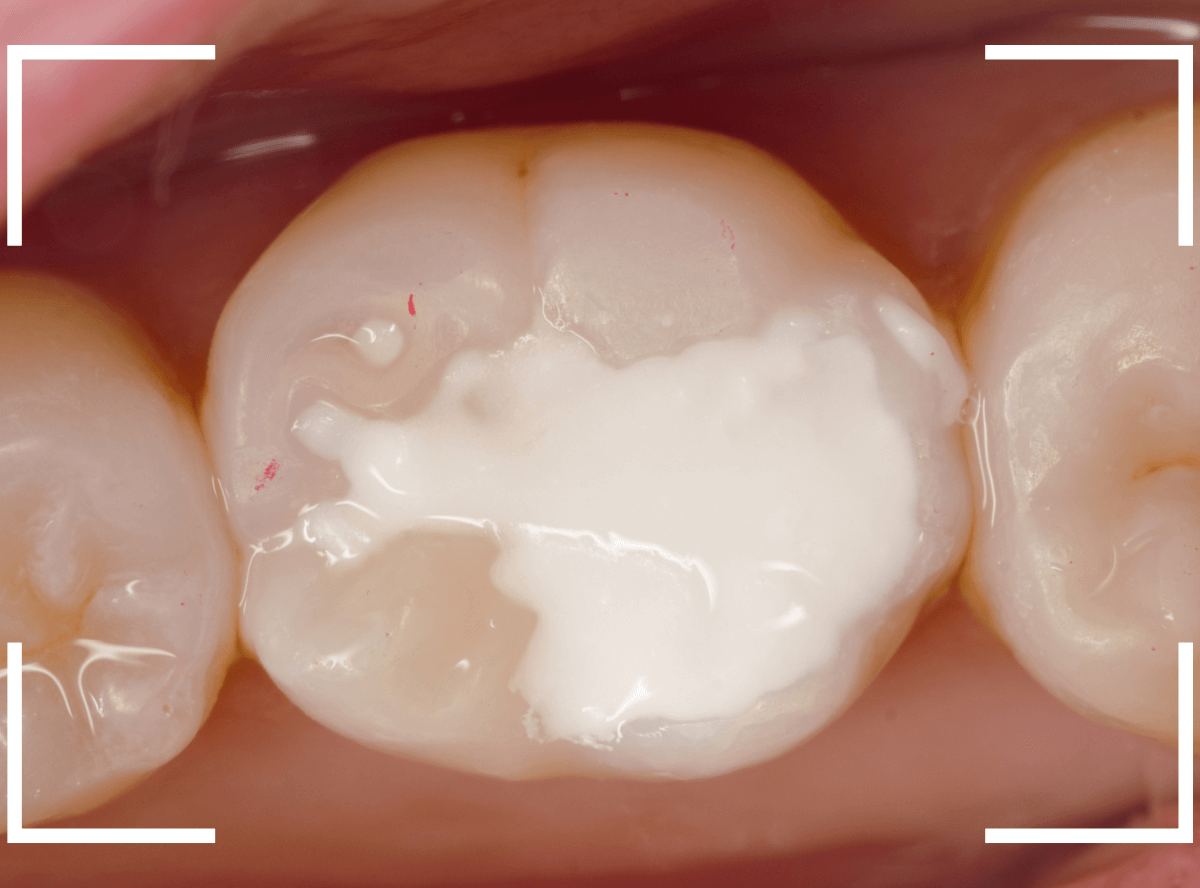

Case.18 虫歯なのは間違いないが、境界がはっきりしない

「つめものが外れて、噛むと痛い」という訴えで来院された患者さんさんです。

一見で、表面が虫歯になっているのと、レジンが劣化しているのがわかります。

レントゲン写真で確認します。

〇部が当該の歯です。

症状もあるので、虫歯が深そうですが、全体がもやっとして、どこからどこまで虫歯なのかはっきりわかりません。

まれに、こんな時もあります。

レジンを外し、虫歯の処置を進めます。

慎重に虫歯を除去し、一安心か、という寸前で(〇部、小さく出血しているところ)露髄してきました。

神経を除去しないとダメかもしれません。。。

神経を保護するお薬をつめて、経過観察します。

痛みが出ませんように。。。